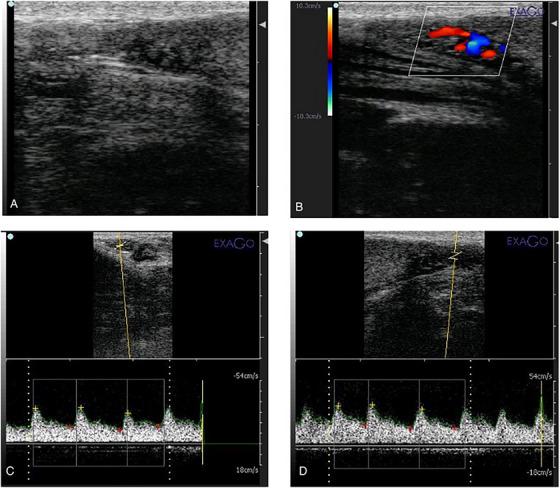

This study investigates the dose-response effects of oral melatonin on reproductive parameters in intact male Pomeranian dogs diagnosed with Alopecia X. Given melatonin's potential therapeutic effects on hair regrowth and reproductive health, this study aimed to evaluate its impact on semen quality, hormonal profiles and testicular haemodynamics. A total of 16 intact male Pomeranian dogs were randomly assigned to four groups: a control group receiving a placebo and three treatment groups receiving melatonin at low (0.1 mg/kg), medium (0.3 mg/kg) and high (0.5 mg/kg) doses, administered twice daily for 45 days. Reproductive parameters, including semen volume, sperm concentration, total sperm count, sperm motility and levels of testosterone and oestradiol 17-ß, were assessed biweekly. Testicular haemodynamics were evaluated using pulsed Doppler ultrasonography. The results showed dose-dependent improvements in semen quality and testicular blood flow, with the highest dose group demonstrating the most significant improvements. However, analysis of the testosterone-to-oestradiol ratio revealed a decrease in the treatment groups, highlighting a complex hormonal response. Although semen quality improved, the study's short duration may not have captured the full spermatogenesis cycle. These findings suggest that melatonin may enhance reproductive function in male dogs with Alopecia X, but further research is needed to clarify its long-term endocrine effects and optimize treatment protocols.

本研究调查了口服褪黑素对诊断为X型脱发的雄性博美犬生殖参数的剂量反应效应。鉴于褪黑素对毛发生长和生殖健康的潜在治疗作用,本研究旨在评估其对精液质量、激素水平和睾丸血流动力学的影响。总共16只雄性博美犬被随机分为四组:一组接受安慰剂的对照组和三组分别接受低剂量(0.1毫克/千克)、中剂量(0.3毫克/千克)和高剂量(0.5毫克/千克)褪黑素的治疗组,每天给药两次,持续45天。每两周评估一次生殖参数,包括精液量、精子浓度、总精子数、精子活力以及睾酮和雌二醇17-β水平。使用脉冲多普勒超声评估睾丸血流动力学。结果显示精液质量和睾丸血流呈剂量依赖性改善,最高剂量组的改善最为显著。然而,对睾酮与雌二醇比值的分析显示治疗组有所下降,突出了复杂的激素反应。尽管精液质量有所改善,但该研究的短疗程可能未涵盖完整的精子发生周期。这些发现表明,褪黑素可能增强患有X型脱发的雄性犬的生殖功能,但需要进一步研究以阐明其长期内分泌效应并优化治疗方案。